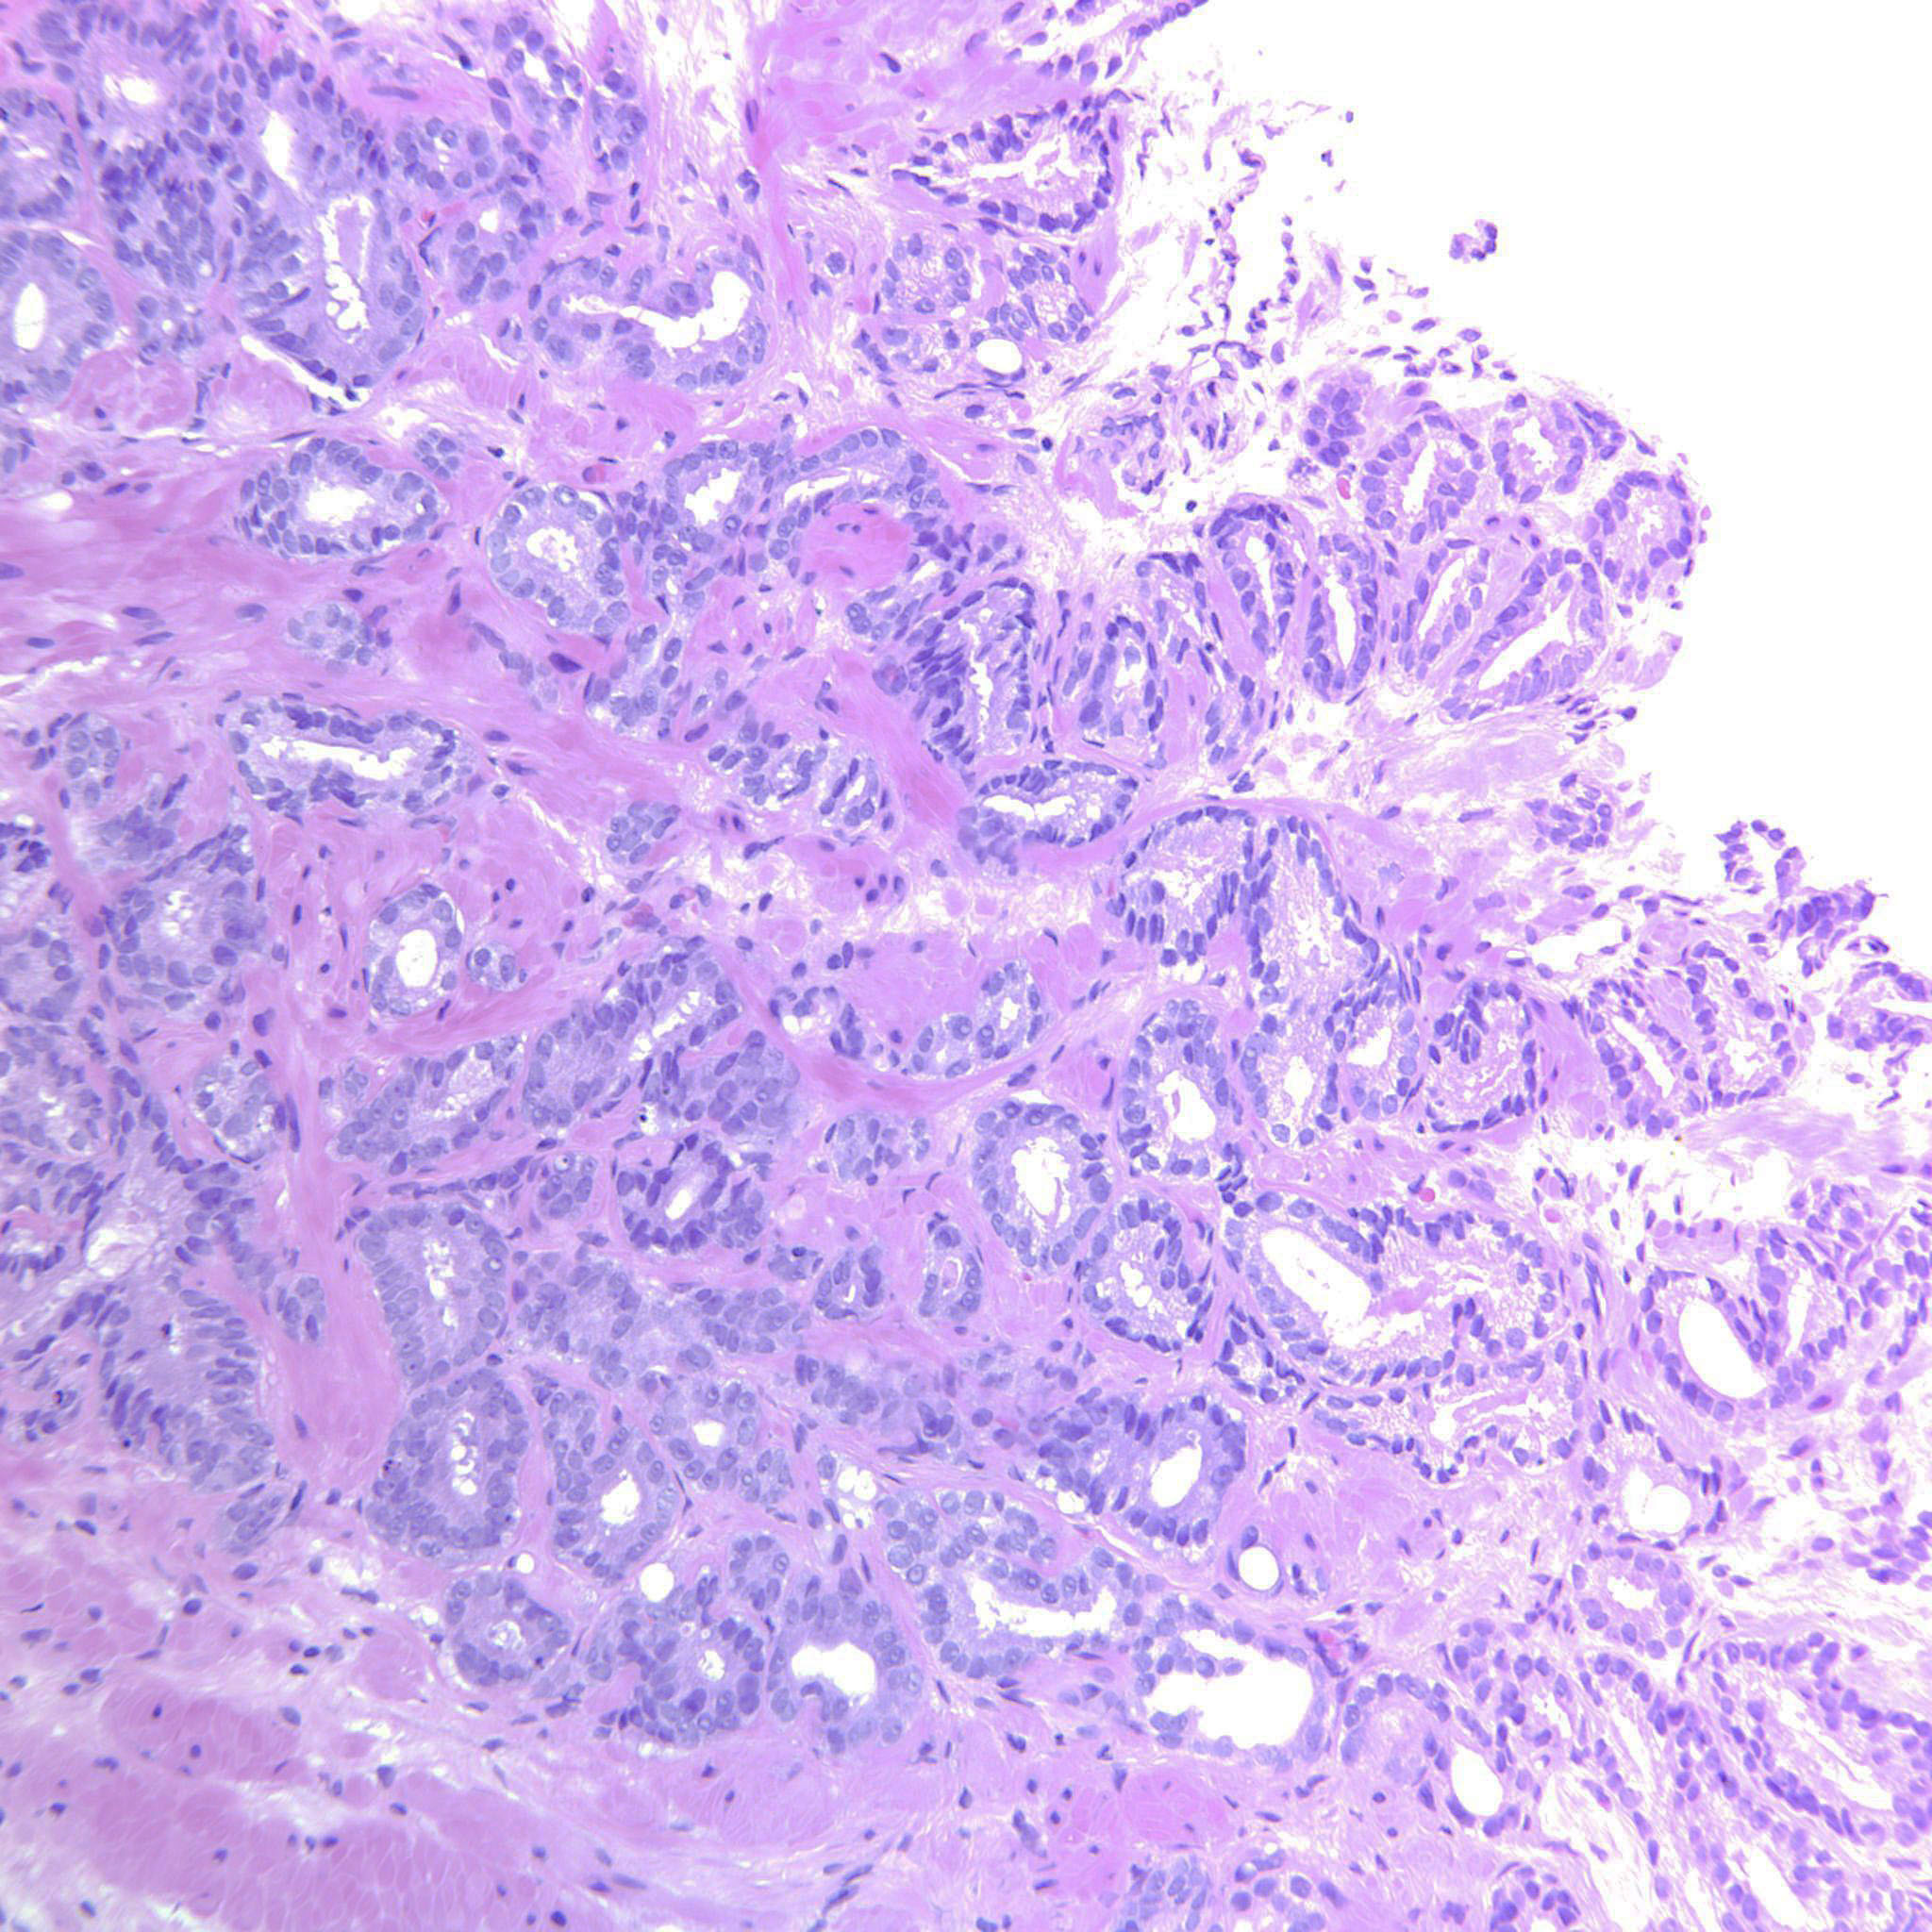

Prostate cancer grading

Case ID: 643